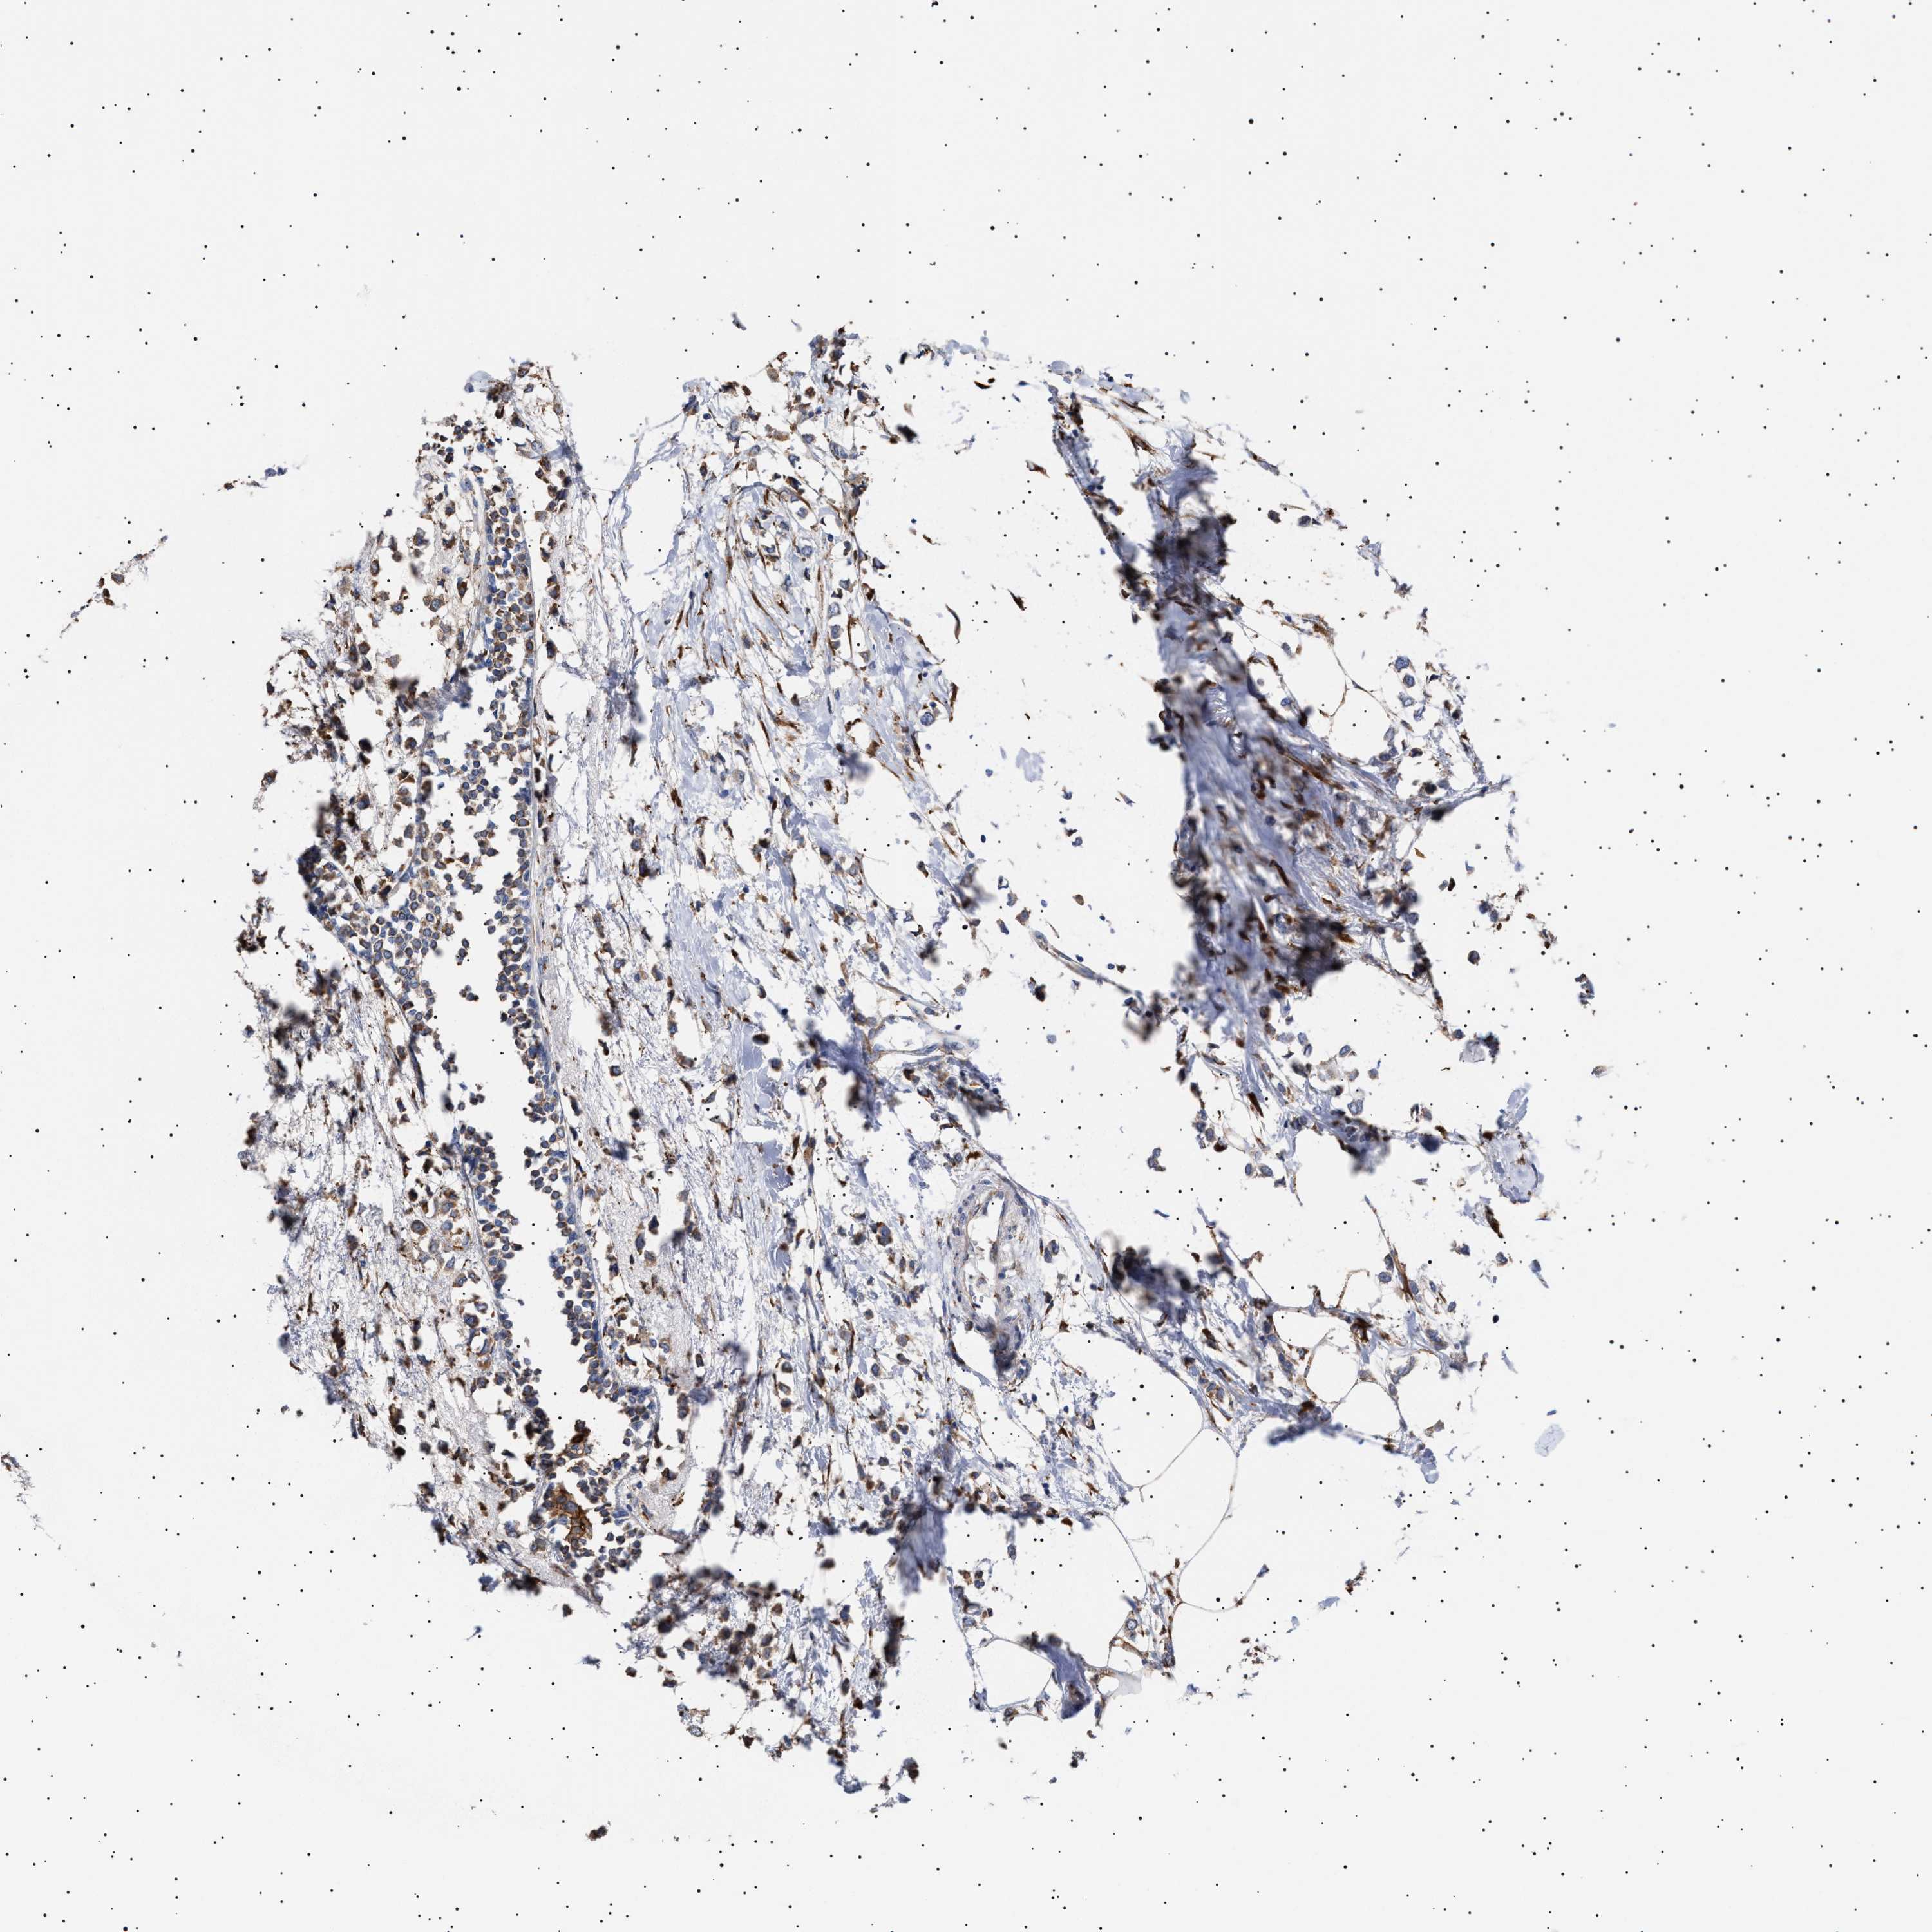

BRCA TCGA BRCA VALIDATION PROTEIN EXPRESSION

ANTIBODIES

AND

VALIDATION